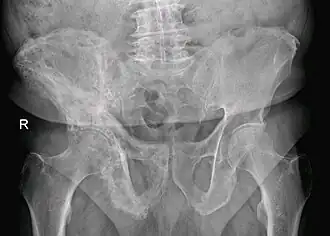

![]() Болезнь Педжета костей таза справа | |

Основным инструментальным методом диагностики является рентгенография. Типичными рентгенологическими признаками являются остеосклероз, чередующийся участками остеолиза, увелечение кости и деформация. Возможно проведение сцинтиграфии костей, которая позволит определить распространённость заболевания и выявить возможные асимптомные поражения костей. При возможном метастатическом поражении костей следует проведение костной биопсии.